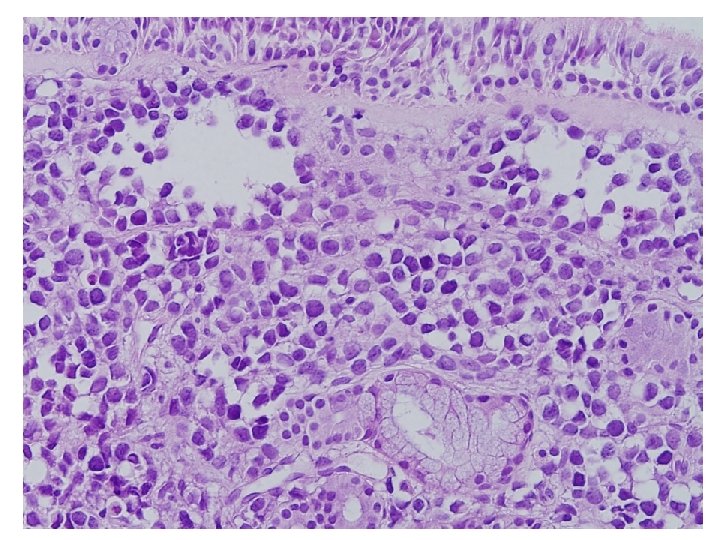

Cytologic features • Cellularity : High • Background : Clear, but necrotic cytoplasmic materials • Dispersed isolated round cells • Cytoplasm : dense, well defined border • Nucleus : small, eccenteric, round or curved, hyperchromatic • Mulinucleated, and binucleated cells • Nucleoli : indistinct, occasionally small nucleoli • Mitosis

Rhabdomyosarcoma • • • High cellularity Small round cell Rhabdoid feature Eccentric hyperchromatic nucleus Occasionally small nucleoli

Diagnosis FNA from left level Ⅲ lymph node : Metastatic rhabdomyosarcoma, alveolar type